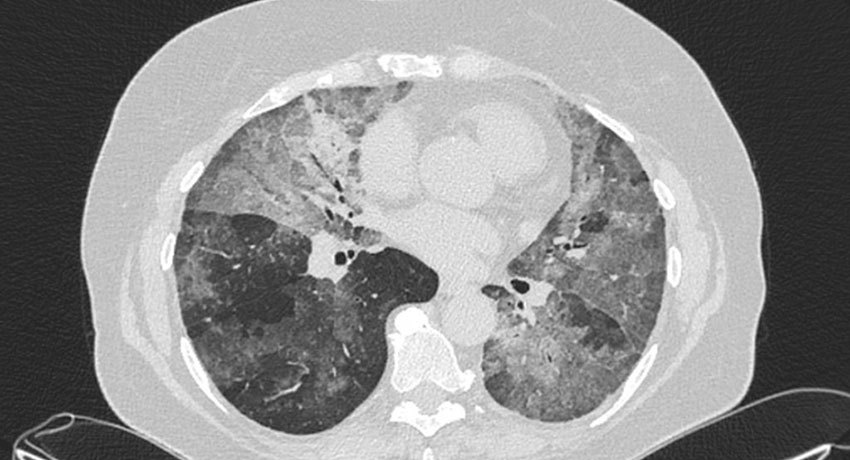

Термин «аденокарцинома» обозначает злокачественные опухоли из железистых клеток, вырабатывающих слизь или другой секрет. В легких они обычно развиваются в конечных отделах дыхательных путей — альвеолах. По сравнению с другими типами рака легкого, аденокарциномы растут относительно медленно, и их чаще удается диагностировать на ранних стадиях. Но если заболевание выявлено на поздней стадии, когда имеется поражение соседних органов, лимфоузлов, отдаленные метастазы, прогноз сильно ухудшается. Как правило, аденокарциномы находятся в периферической части легкого.

На ранних стадиях аденокарцинома легкого обычно не вызывает симптомов. Такие опухоли могут быть случайно диагностированы во время рентгенографии или компьютерной томографии грудной клетки по поводу других заболеваний.

Обычно обследование начинают с рентгенографии грудной клетки. Если во время нее выявлены патологические изменения, проводят компьютерную томографию. Может быть назначена МРТ, ПЭТ-КТ. Во время позитронно-эмиссионной томографии в организм пациента вводят безопасный радиофармпрепарат, который накапливается в опухолевых очагах и делает их заметными на снимках, выполненных с помощью специальной аппаратуры.